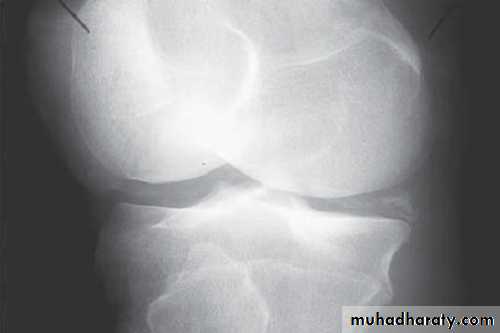

Radiographs

Radiograph of the joint: Although frequently normal, a radiograph may disclose important information.It may help in diagnosing an unsuspected fracture, osteonecrosis, osteoarthritis, or a juxtaarticular bone tumor.

The presence of chondrocalcinosis, a radiologic feature of CPPD disease, increases suspicion for a pseudogout attack.

Tumor, chronic fungal or mycobacterial infection, and other indolent destructive processes may be revealed.

A contralateral joint radiograph for comparison may be useful, especially in children.